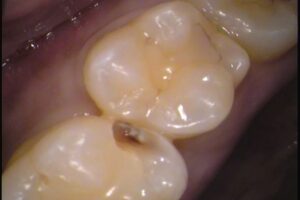

例えば、この写真には黒いところが何か所かあります。

これは虫歯でしょうか?

その①歯の溝の黒

矢印の歯ですが、

患者さんの多くが虫歯かと悩む、このような歯。

歯に黒く筋が入っています。

これは溝に入り込んだ「着色」で虫歯ではありません。

その②詰め物の隙間の黒

今度はこちらの矢印の歯ですが、

まだら模様の様に黒い筋があります。

こちらは詰め物をした箇所に着色が入り込んでいます。

以前、レジンというプラスティック樹脂で詰め物がしてある歯なのですが、詰め物と歯との接着が剥がれ、その隙間に着色が入り込んでいます。

そのため詰め物の形に沿って黒い筋となって見えています。

治療が必要ないかというと一概に言えず、先ほどの「歯の溝」と違い人工的な隙間となっているため虫歯が入り込んでいる可能性もあります。

エックス線検査(レントゲン検査)など専門的な検査を行い、虫歯を確認しましょう。